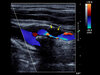

Bildunterschrift: Farbduplex-Sonographie der Halsschlagader: Die Pfeile zeigen eine hochgradige Verengung der inneren Halsschlagader (Carotis-Stenose).

Bildrechte: M. Reinhard, Klinik für Neurologie und Neurophysiologie, Universitätsklinikum Freiburg